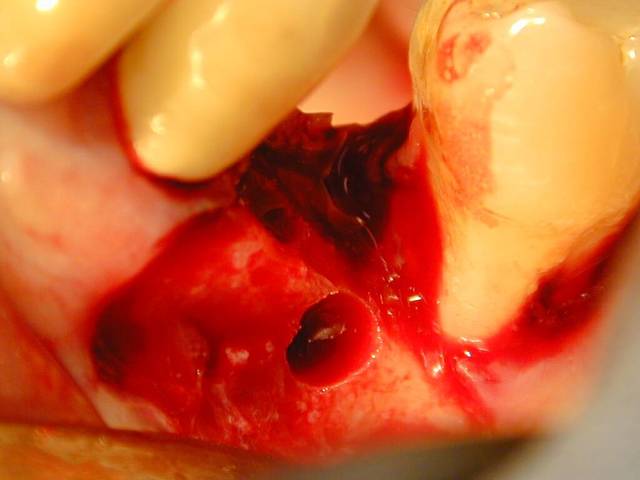

Cher Monsieur alhoun dit le Sakharov du Forum, si vous voulez bien aider un petit jeune qui débute, je prépare mon polycop de bizarrodontologie clinique et je voulais votre avis sur ce summers non conventionnel dans un cadre un peu étriqué.

Hé Galilée c'est parce que la 7, mème d'aprés les critères des penseurs de Capbreton a un avenir limité et va être extraite et implantée. Or implanter là c'est pas forcément de la tarte.

Dans l'espace interdentaire le sinus est invaginé. Donc plutot qu'extraire et greffer pourquoi ne pas summeriser entre les deux en comptant sur la vascularisation venant de la dent puis on extraiera ensuite. Torquemada aussi peut donner son avis, hein. Voyez mes efforts pour rétablir la paix sur ce forum, et resserer des liens distordus par les invectives de mes confrères vétilleux.